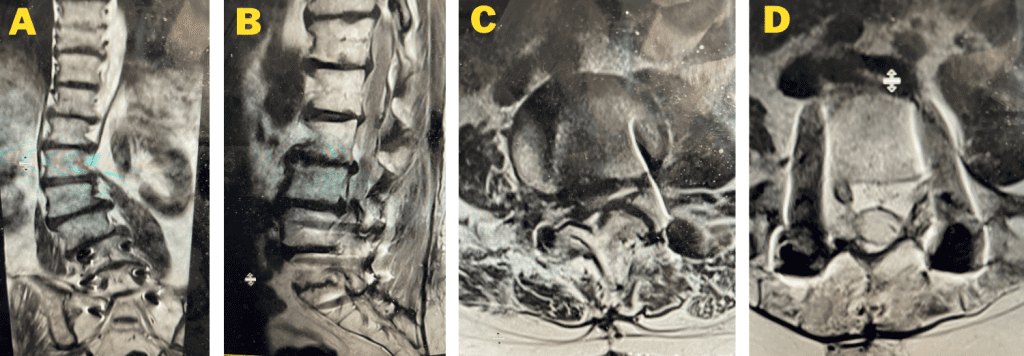

This 72 year old female had a long history of low back pain, leg pain, and scoliosis for which ten years ago she had a lumbar laminectomy followed by an instrumented L4-S1 fusion a year later. Since that time she had progressive low back pain and right lower extremity, weakness, and numbness. She presented with her leg symptoms being the biggest problem. MRI demonstrated a degenerative scoliosis with severe stenosis above the L4-S1 laminectomy and instrumented fusion. She had severe L2-3 and L3-4 stenosis. (Figs.3a,3b,3c 3d). After failing conservative management, she underwent an L2-L4 revision laminectomy and in situ fusion. She did well postoperatively. Considerations in performing a revision spine surgery is scar formation which initially makes it challenging to identify landmarks even in the region above that was not previously operated on. And of course during the dissection of compressive material on the dura, it is difficult to identify planes of separation and therefore an increased risk of a CSF leak. It was felt because of the severity of the scoliosis and her age we augmented the laminectomy with an in situ fusion, or a fusion with just bone graft without instrumentation. It is controversial whether a fusion is actually necessary in the case of a stable degenerative scoliosis with stenosis but the accepted approach is to perform a fusion If an instrumented fusion is considered it would require at least a T11-pelvis fusion. Since we performed only a 2 level laminectomy with a severely osteophytic spine, we compromised with an in situ fusion, reducing blood loss, operating time, and risk for infection. Because of the degree of spondylotic disease as a result of the stresses and strains on the spine given the scoliosis, the spine attempts to auto stabilize by forming these buttresses of arthritic material.

Fig 3a: Coronal T2-weighted MRI demonstrating significant detro lumbar degenerative scoliosis with a prior L4-S1 instrumented fusion. Note lateral listhesis of the L3-4; Figs 3b and 3c: Sagittal and axial T2- weighted MRIs showing severe lumbar stenosis above the prior L4-S1 fusion; Fig 3d showing an axial image T2-weighted MRI at the level of the prior L4-5 portion of the fusion showing no recurrent stenosis